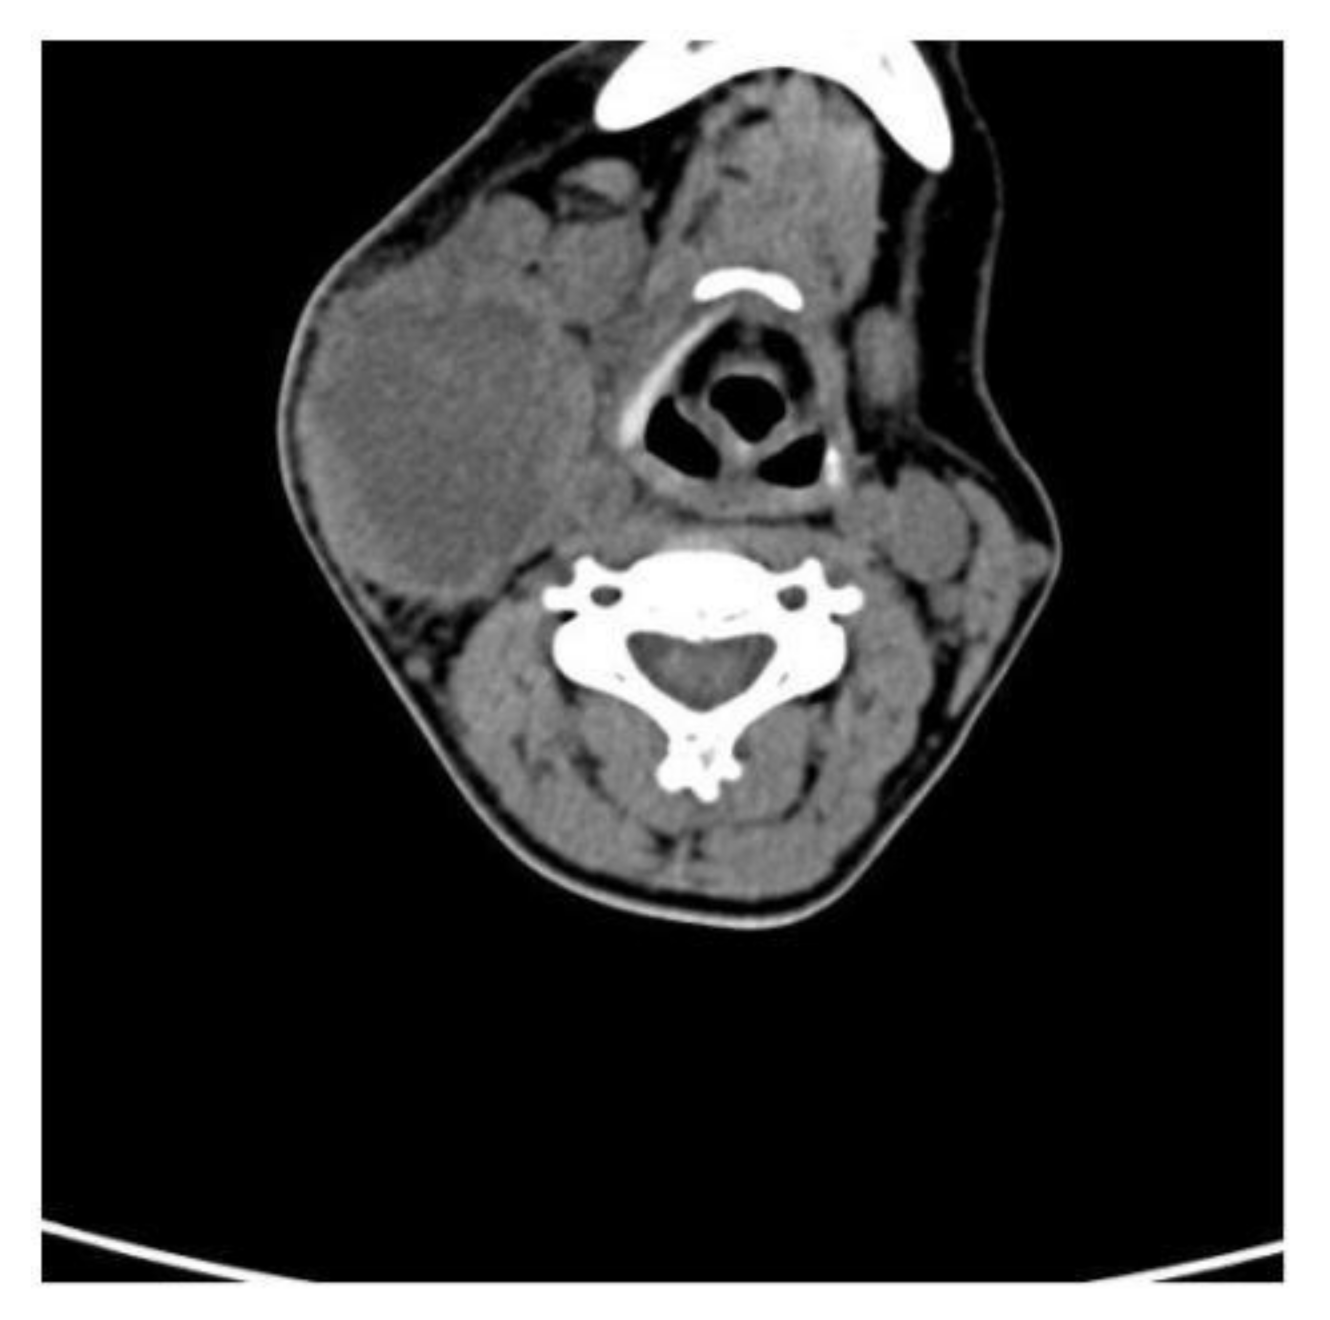

Contrast CT showed that the pseudo-tumoral lesion of the right lateral cervical region measured about 6 × 5 × 6 cm and was characterized by a hypodense probably necrotic–colliquative core, hyperdense internal shoots, thick walls, and jagged edges (Figure 1).

Figure 1. Contrast CT of the neoplasm. Description is given in the main text.